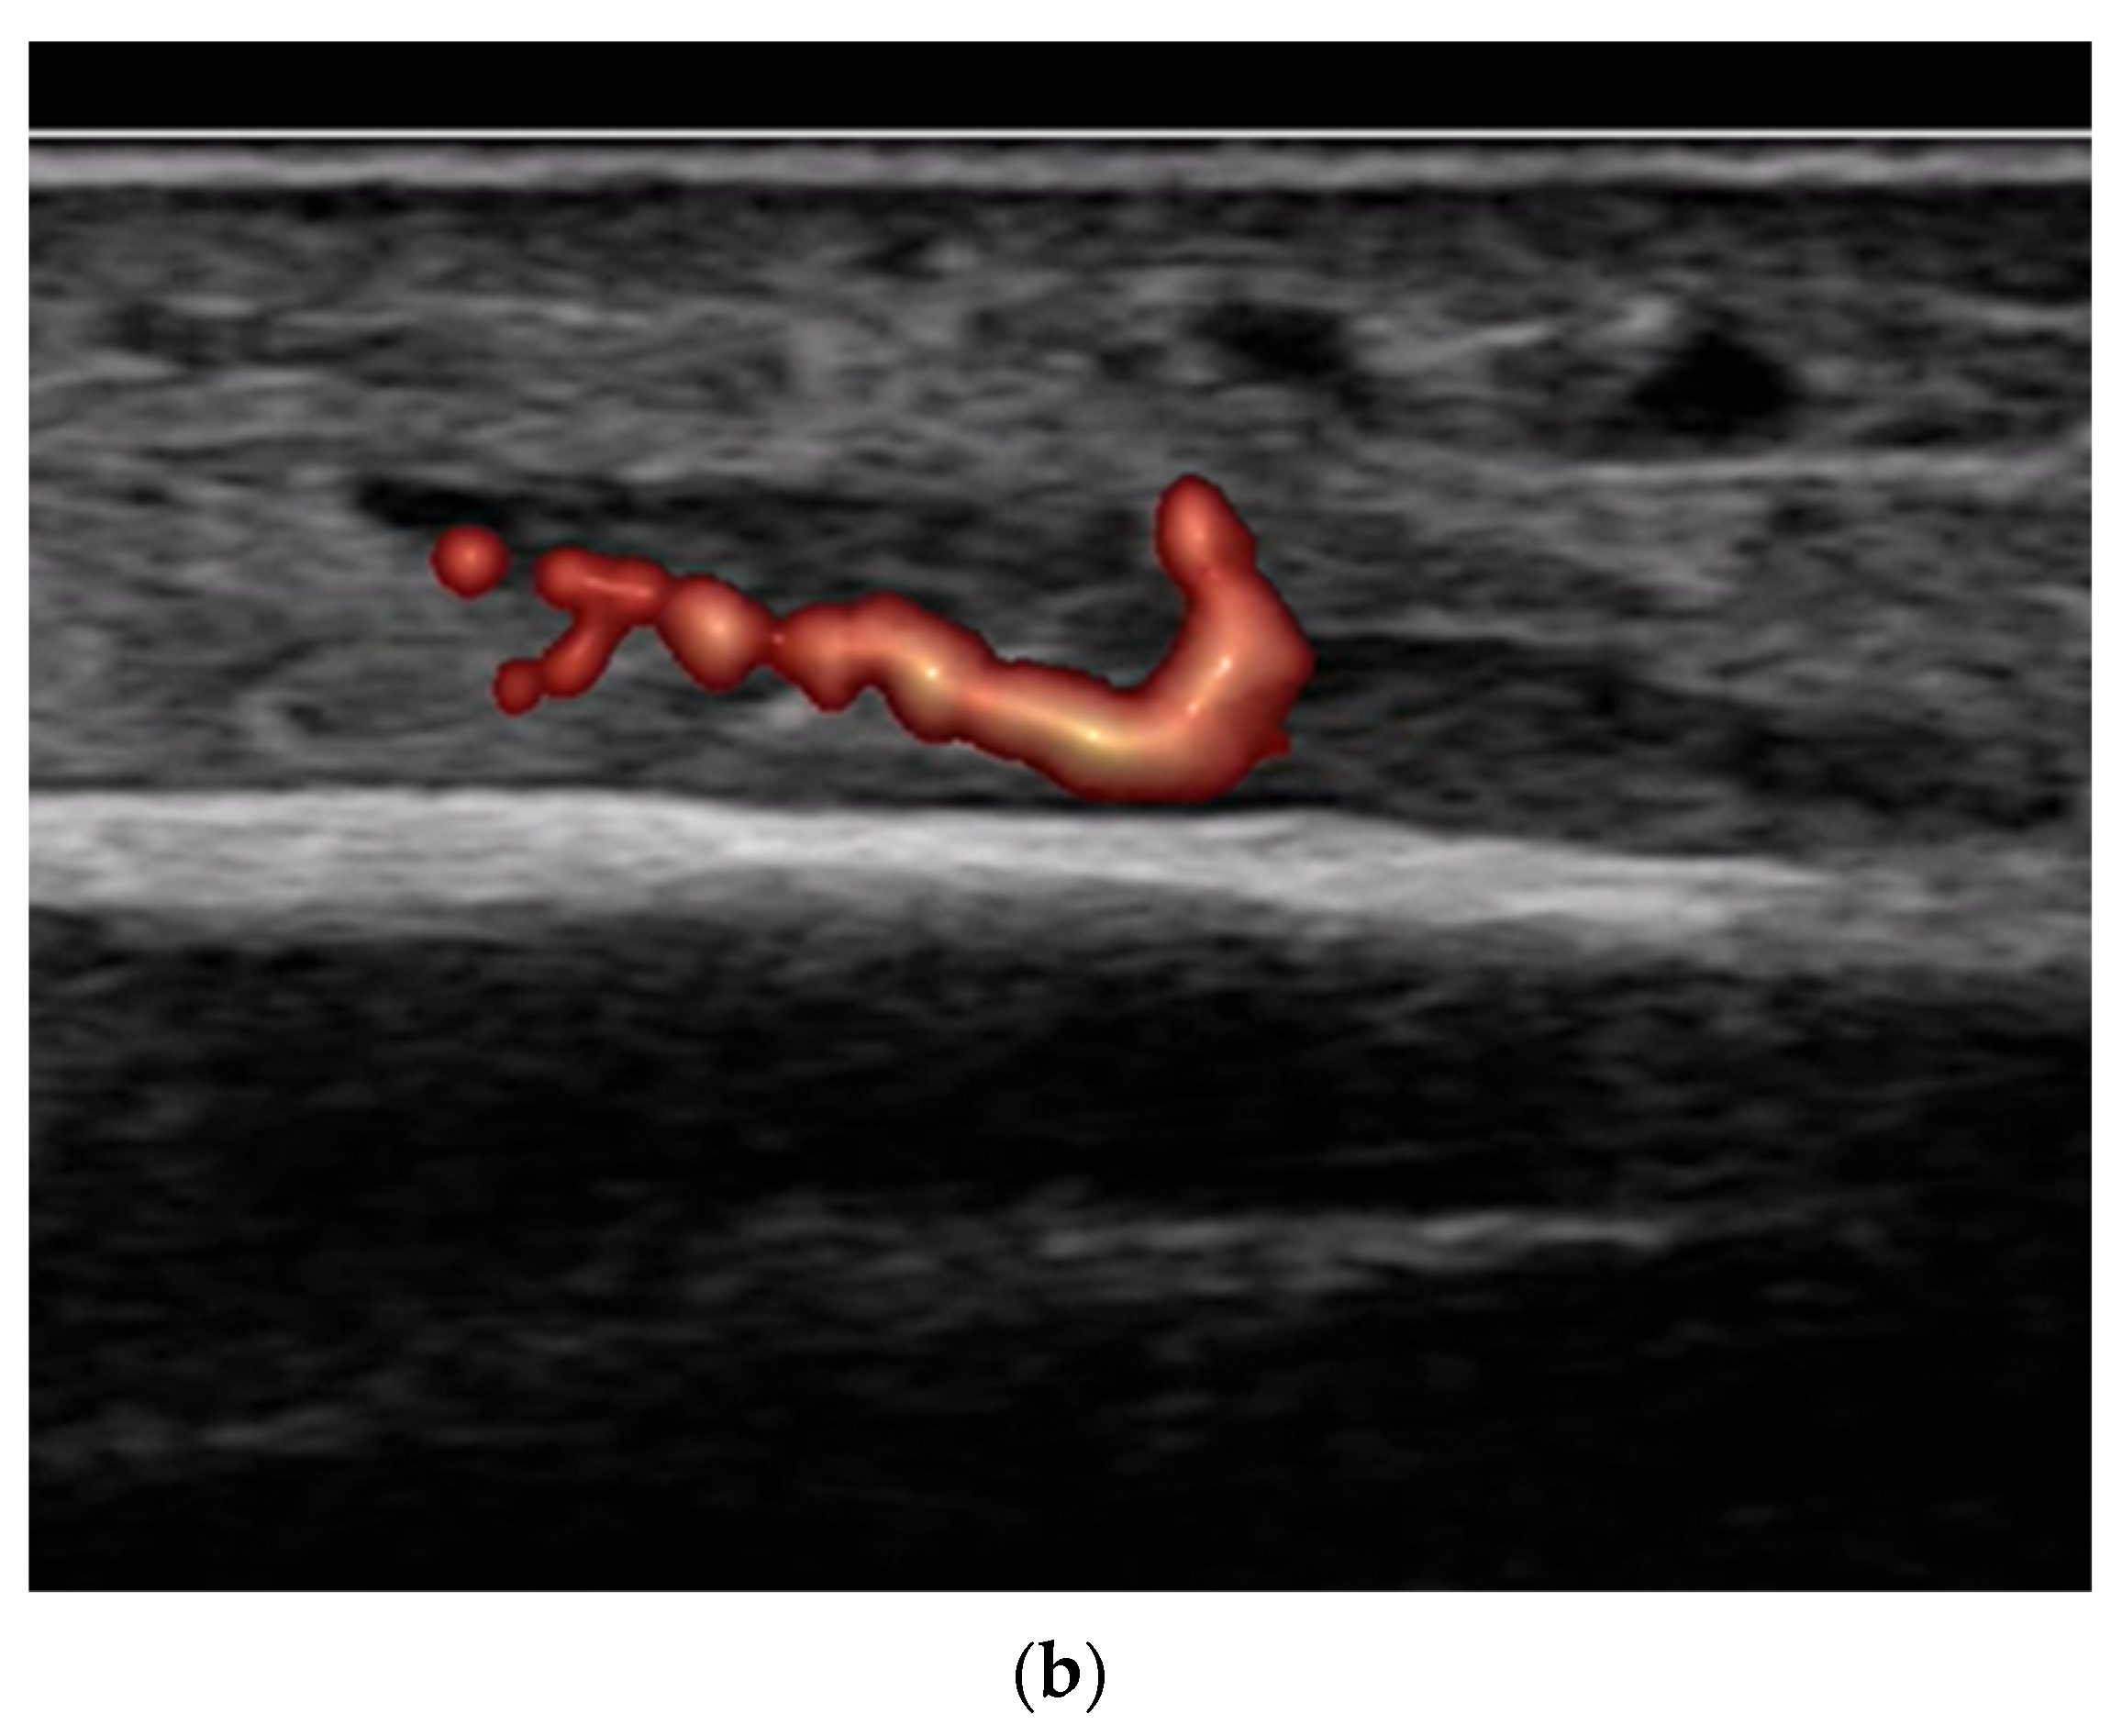

4.2. Sonoanatomy of Fractures [Figure 5, Figure 6, Figure 7 and Figure 8]

- Local hematoma or soft tissue edema: fluid collections or increased echogenicity near the fracture site indicating bleeding and inflammation.

- Periosteal thickening or elevation: the periosteum may appear thickened or lifted due to injury or early callus formation.

- Use of color and power Doppler: When employing Doppler techniques to assess vascularity related to inflammation or healing, care must be taken to avoid excessive probe pressure. Over compression of the tissue can collapse small vessels, leading to false-negative findings.